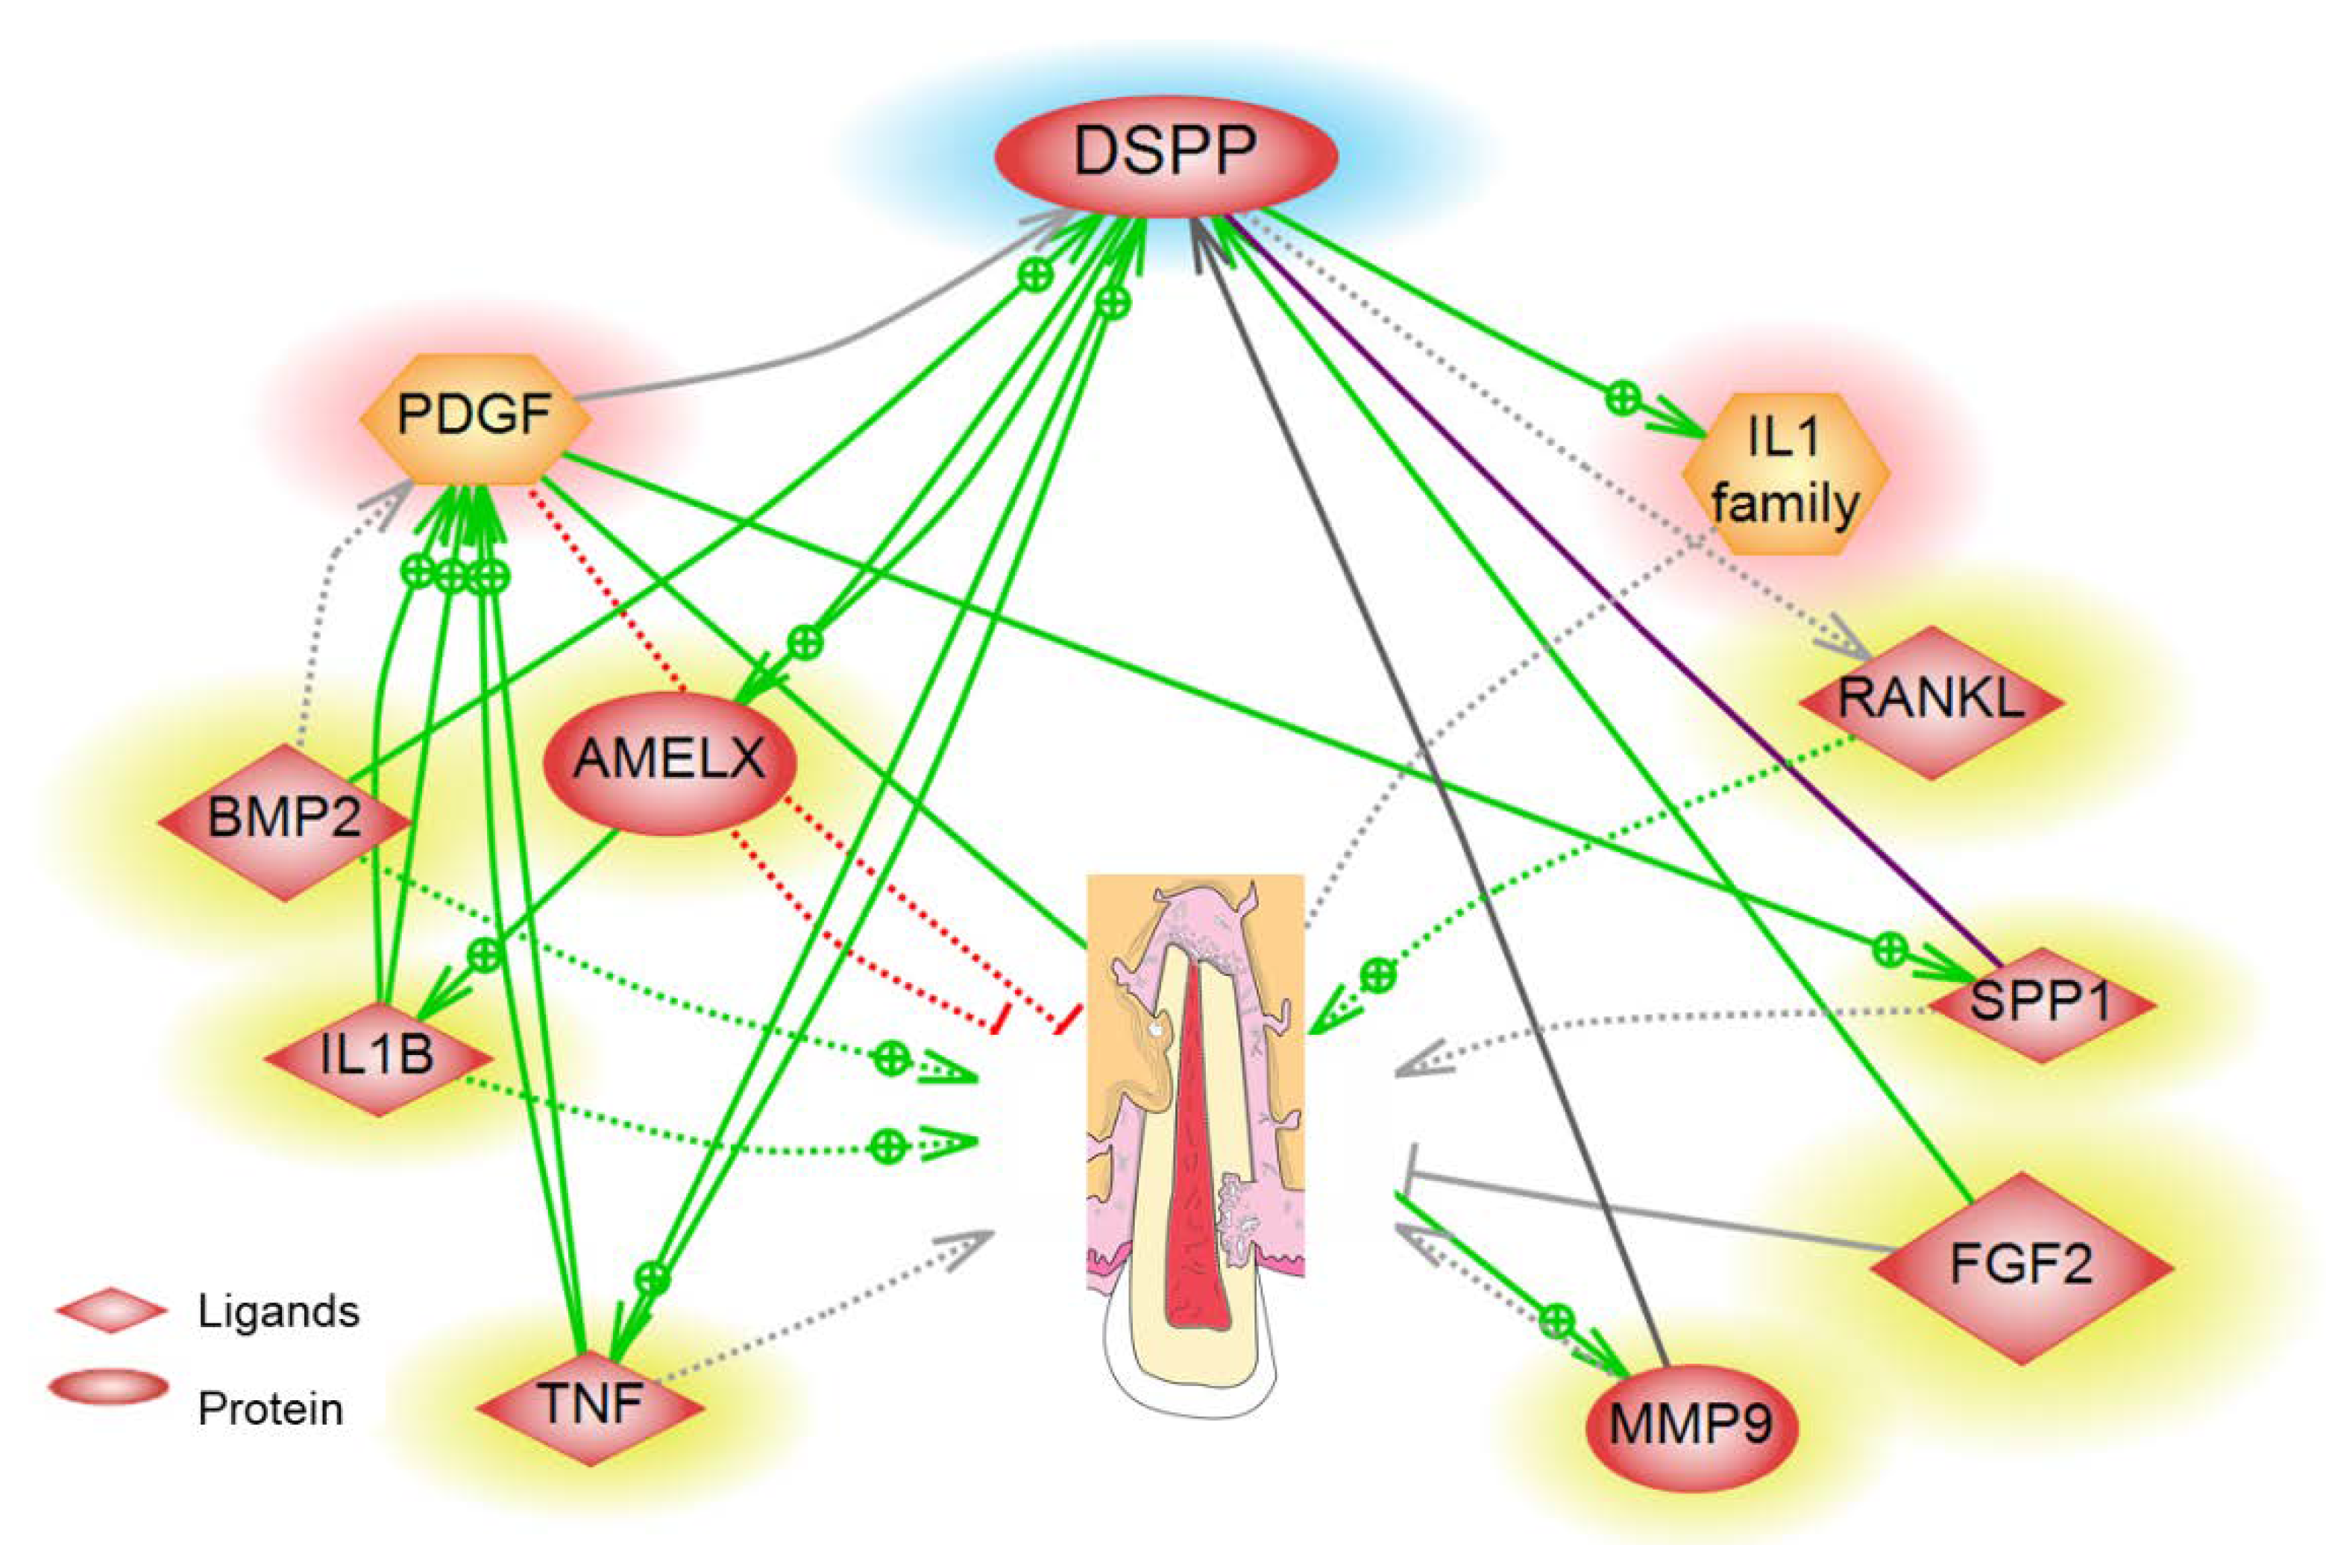

4. Biomarkers Associated with ERR

| Biomarker | Pathway/Function | Detection Site | References |

|---|---|---|---|

| RANKL/OPG | RANKL/RANK/OPG Signaling Pathway | GCF | Alyahya et al. [37], Fukushima et al. [38], Low et al. [39], Tyrovola et al. [40], Yamaguchi et al. [13] |

| Interleukin-1B | Inflammatory Pathway | GCF | Bletsa et al. [41], Kulkarni et al. [42], Yao et al. [43] |

| TNF-Alpha | Inflammatory Pathway | GCF | Kapoor et al. [12], Bletsa et al. [41] |

| Dentin Sialoprotein (DSP) | BMP/Smad, JNK, ERK, MAPK, and NF-κB signalling | GCF | Ritchie et al. [36], Kumar et al. [35], Kereshanan et al. [44], Lombardo et al. [45] |

| Dentin phosphoprotein (DPP) | AKT and mTOR | GCF | Mah et al. [34], Silva et al. [46], Yuan et al. [33] |

| Interleukin-6 | Notch Signaling | GCF/PDL | Yamaguchi et al. [13] |

| MicroRNA-29 | Osteoclast regulation | GCF | Atsawasuwan et al. [47] |